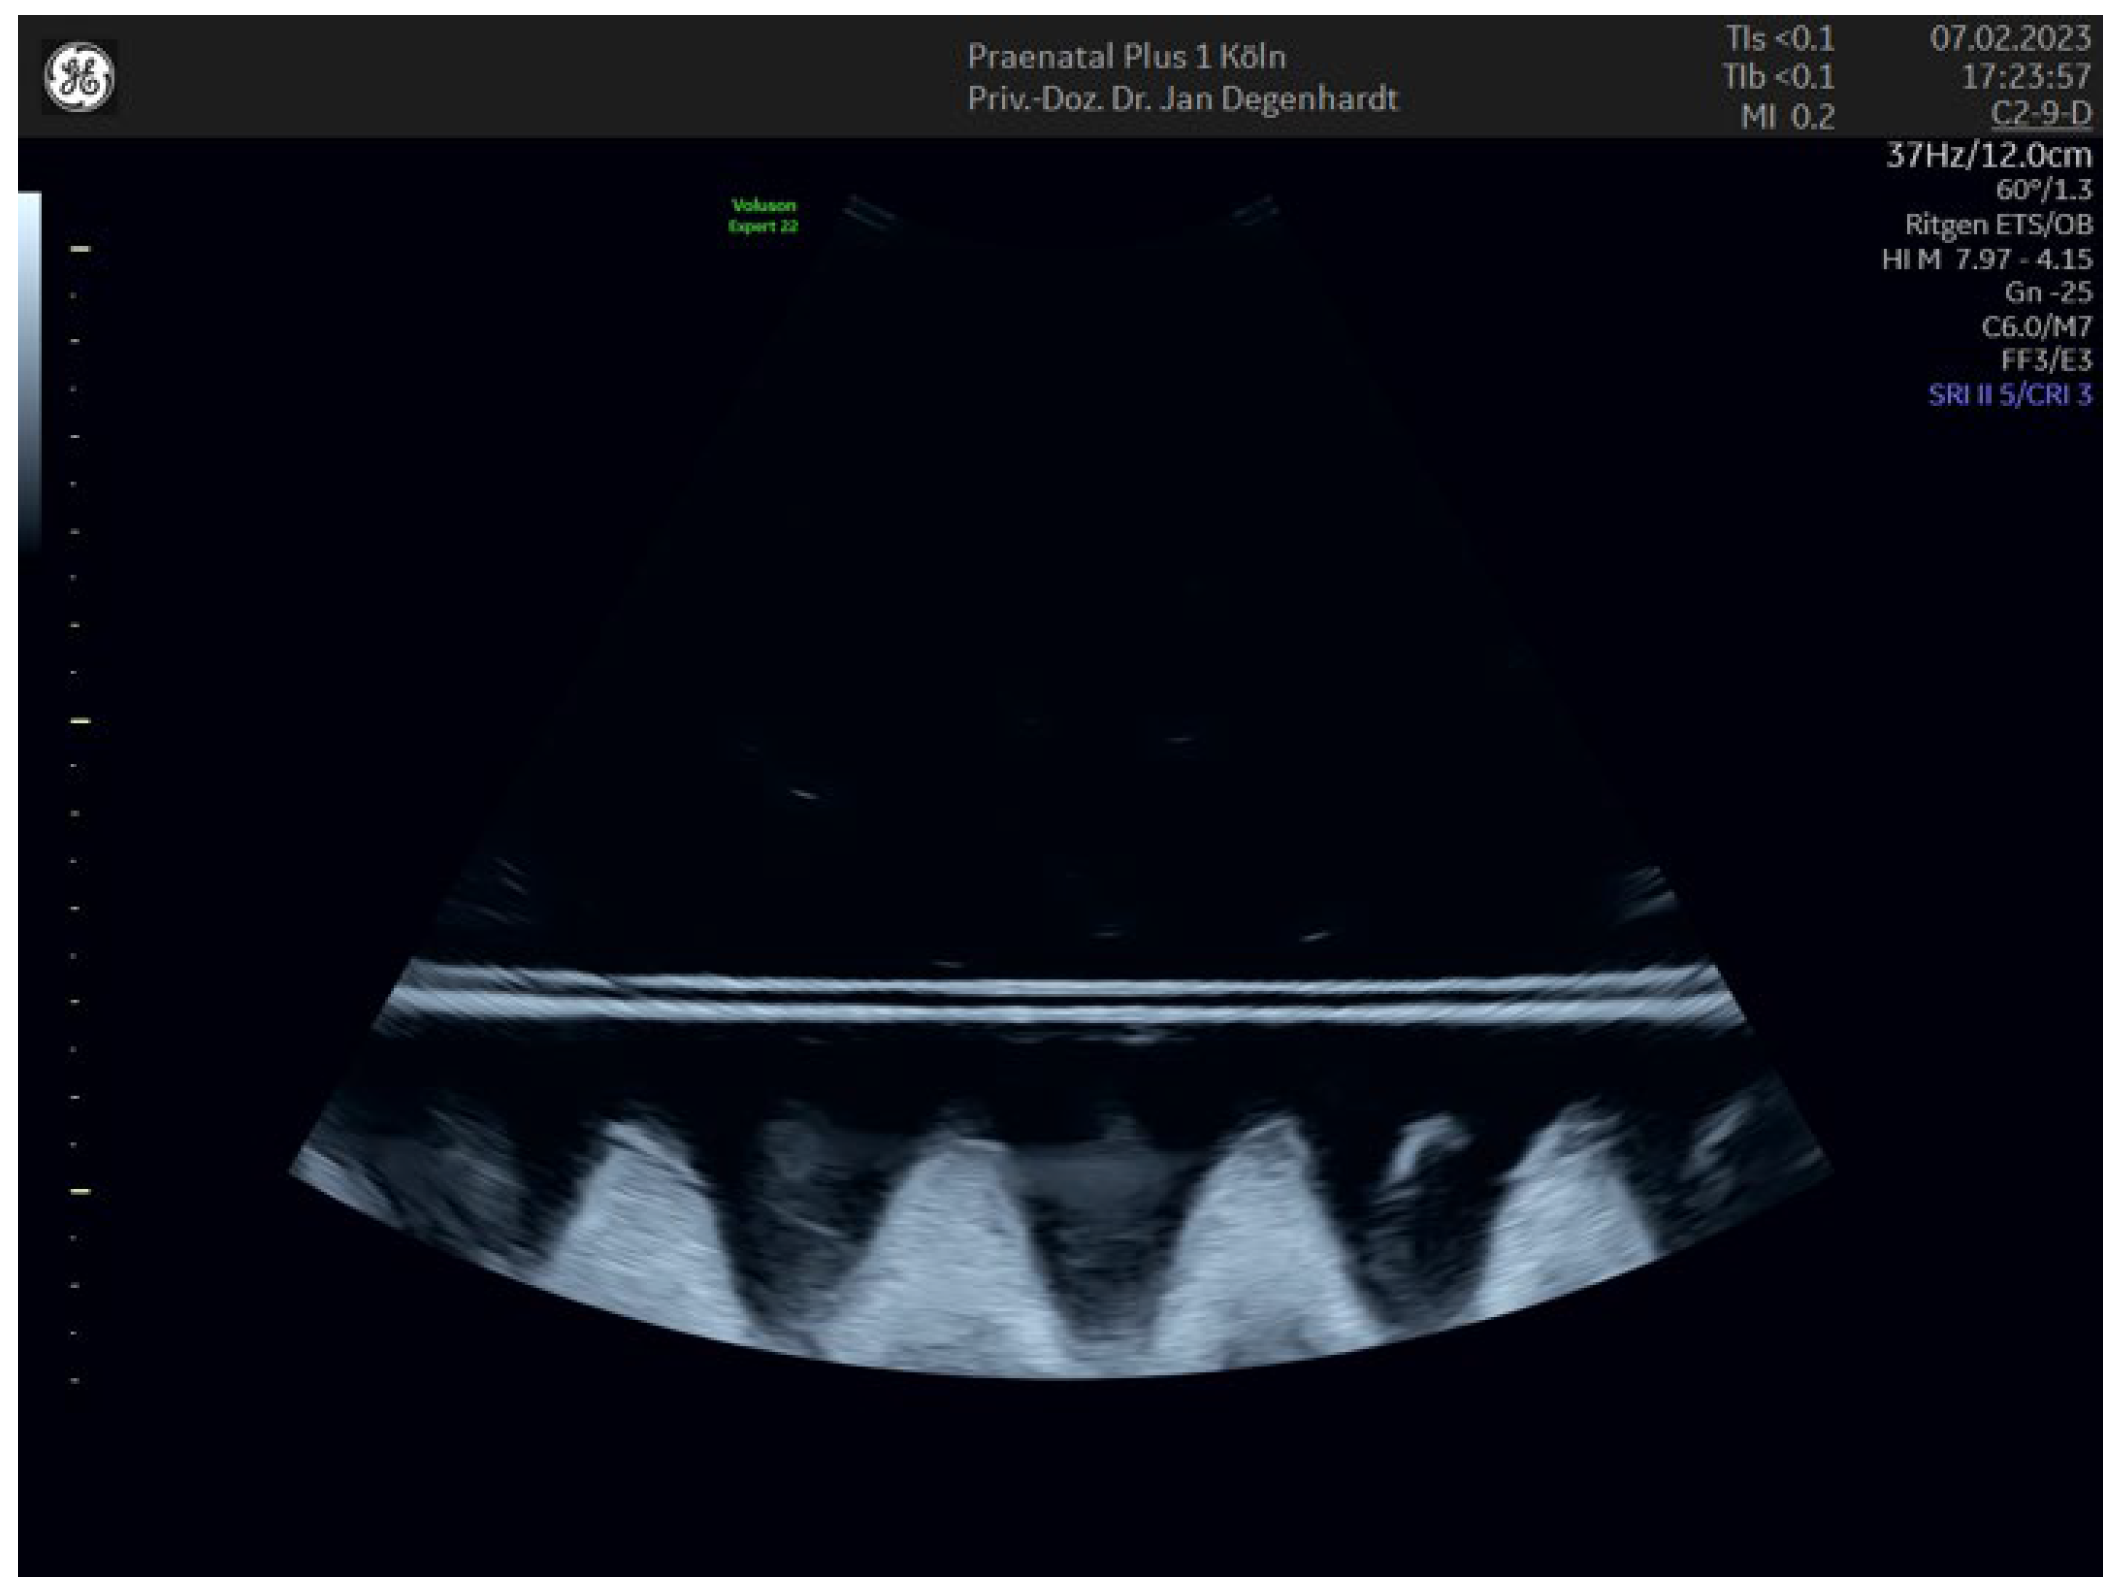

2.1. Nuchal Translucency with and without ‘Radiant’ Applied

3.1. Nuchal Translucency with and without ‘Radiant’ Applied